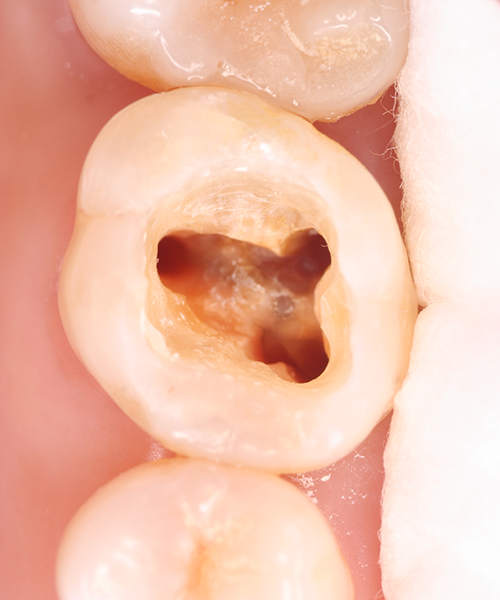

感染部分の除去

根管治療用の器具を使って、細菌に感染してしまった根管内の神経などを除去します。